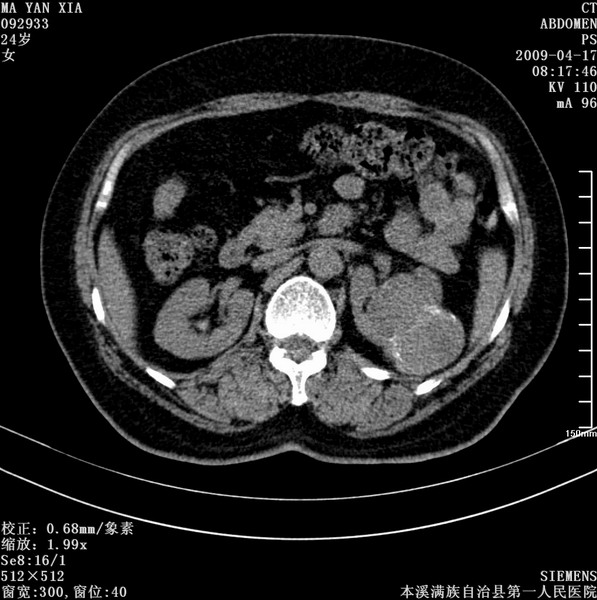

标题: CT19443:肾脏肿瘤两个区强化不一样。 [打印本页]

标题: CT19443:肾脏肿瘤两个区强化不一样。

女,51岁,体检时发现肾脏占位,建议ct增强。无任何自觉症状。

典型的不均匀强化,左肾癌